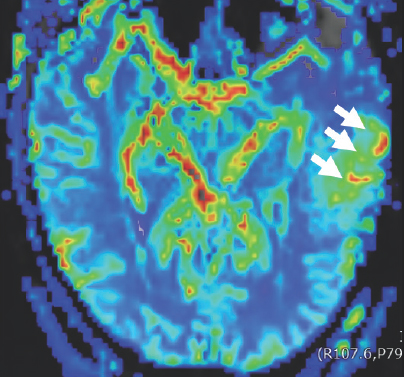

Unfortunately, an MRI scan in October of 2019 revealed worrisome imaging of potential local progression of the tumor (Fig. 2.1–2.3). In addition to this troubling discovery, abnormalities in Columbus’s neuro-cognitive capacity, such as issues with his memory and word-finding capabilities, were gradually becoming more pronounced. This word-finding difficulty showcased itself through his inability to retrieve words for use in regular speech, despite his retention of the ability to understand the English language. To treat these new symptoms, Columbus was put on the steroid dexamethasone.

Dark blue, green, light blue, orange, red, and yellow colors are scattered within a blue boarder. Three white arrows point to a green blob on the right side of the image that has two sickled ovals that are red, orange, and yellow in color.

FIGURE 2.3 Brain MRI before surgery. Further exploration with advanced perfusion MRI demonstrates that this mass contains areas of moderately increased cerebral blood volume (CBV) (white arrow) suggestive of a tumor.